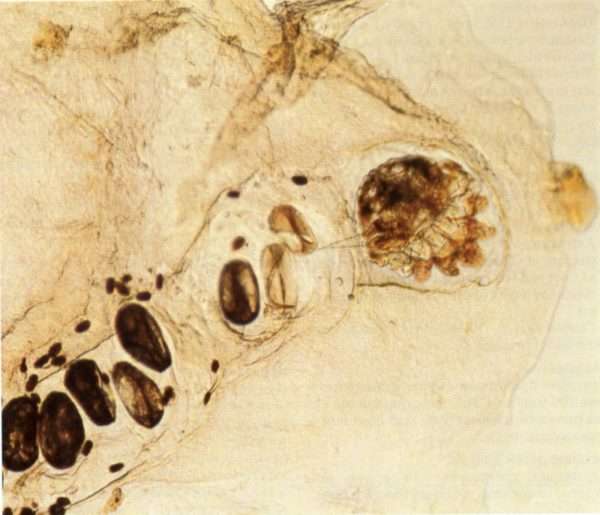

Sarcoptes scabiei – широкоовальный клещ бело-желтого или полностью белого цвета. Длина самых маленьких представителей составляет 0,14 мм. Они поражают всю поверхность тела и вызывают саркоптоз. Заподозрить их появление можно по тонким светло-серым линиям с небольшим пузырьком на конце, возникающим на пораженных участках.

Sarcoptes scabiei представляет собой форму широкого овала белого или желто-белого цвета длиной 0,14 мм. Поражение, как правило, происходит по всему телу. Определить их можно при помощи появления линий светло-серого цвета с маленькими пузыриками в конце. Также есть еще один вид клеща, относящийся к данному заболеванию — Sarcoptes canis.